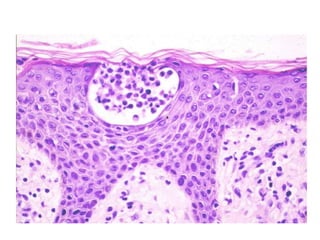

Linfocitos atípicos epidermótropos, aislados o agrupados en tecas, que predominan en la parte

inferior de la epidermis y se caracterizan por un núcleo de tamaño pequeño

a mediano, hipercromático.

La inmunohistoquímica muestra su naturaleza T linfocítica CD3(+).